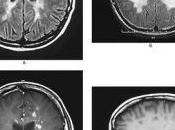

Cellules, AVC et SEP.

Lu il y a quelques jours sur: http://www.radio-canada.ca/regions/Quebec/2009/01/27/006-cellules_avc_recherche.shtmlAccident vasculaire cérébral Des cellules pou... Lire la suite

Publié le 31 janvier 2009 JOURNAL INTIME, MALADIES, SANTÉ, TALENTS -

Nouvelles SEP du jour!

Les alertes sclérose en plaques de google: sur 20mn.fr: Sclérose en plaques: une transplantation de cellules pour «inverser le cours de l'invalidité» Créé le... Lire la suite

Publié le 30 janvier 2009 JOURNAL INTIME, MALADIES, SANTÉ, TALENTS -